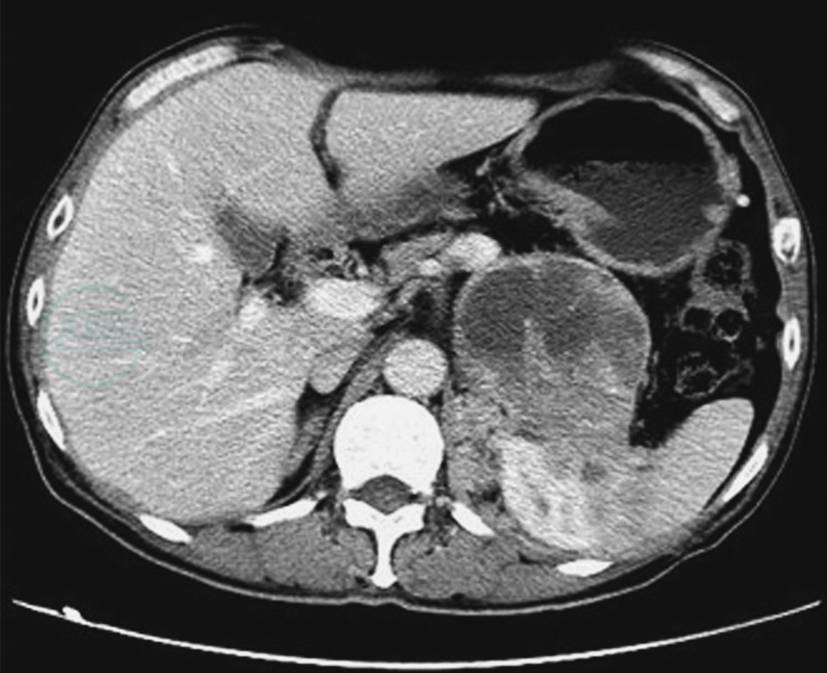

图13中央-边缘坏死

A~D.良性嗜铬细胞瘤不同形态及分布的坏死;E.左侧恶性嗜铬细胞瘤的伴中央-边缘坏死